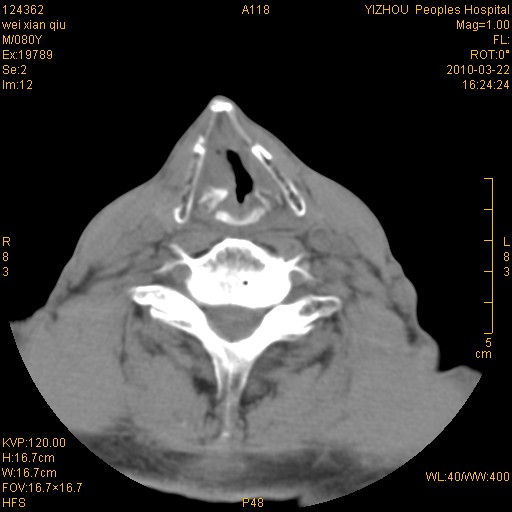

男,80岁.声嘶三月余.

喉前庭右侧壁明显增厚,并见向内突出的软组织密度新生物,表面光滑,其后方软组织层次尚清晰,多考虑:喉部乳头状瘤!建议喉镜并病检!

右侧声们下区新生物

考虑喉癌;建议行喉镜检查(活检)进一步明确诊断。